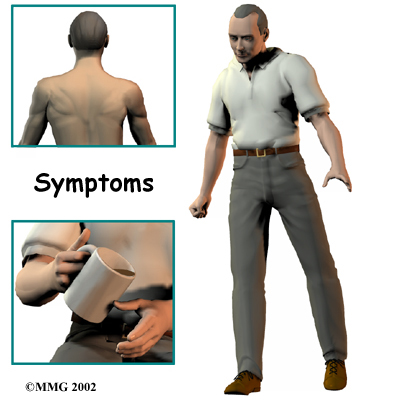

Cervical stenosis usually develops slowly over a long period of time. This is partly because degeneration in later life is the main cause of spinal stenosis. Symptoms rarely appear all at once when degeneration is causing the problems. A severe injury or a herniated disc may cause symptoms to come on immediately.

The first sign to appear in some patients is a change in the way they walk. They don't realize this problem is coming from their neck. But pressure on the spinal cord in the neck can affect the nerves and muscles in the legs, leading to changes in the way they walk. Eventually their walking pattern gets jerky and they lose muscle power in the legs. This is called spasticity.

Most patients also have problems in their hands. The main complaint is that their hands start to feel numb. Others feel clumsy when doing fine motor activities like writing or typing. The ability to grip and let go of items becomes difficult because the muscles along the inside edge of the palm and fingers weaken.

Shoulder weakness also develops in many patients. This happens most often when the spinal cord is compressed in the upper part of the neck. Most affected are the shoulder blade muscles and the deltoid muscle, which covers the top and outside of the shoulder. These muscles weaken and begin to show signs of wasting (atrophy) from not getting nerve input.

The area where the spinal cord is compressed in patients with stenosis is very close to the nerves that go to the arm and hand. The problem that compresses the spinal cord in the neck may also affect the nerves where they leave the spinal column. Nerve pressure can cause pain to radiate from the neck to the shoulder, upper back, or even down one or both arms. It can also cause numbness on the skin of the arm or hand and weakness in the muscles supplied by the nerve.

Pressure against the spinal cord also creates problems with the bowels and bladder. Mild spinal cord pressure makes you feel like you have to urinate more often. But it also makes it difficult to get urine to flow (urinary hesitancy). Moderate disturbances cause people to have a weak flow of urine, making them dribble urine. They also have to strain during bowel movements. In severe cases, people aren't able to voluntarily control their bladder or bowels. This is called incontinence.